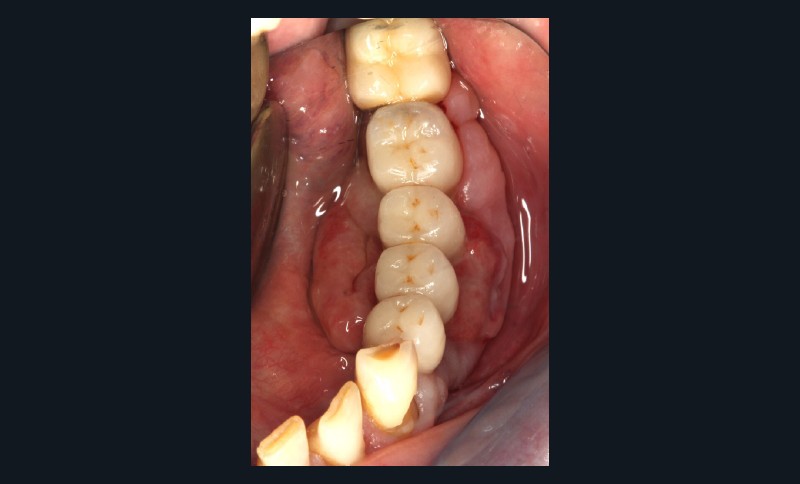

Question 1. Le carcinome épidermoïde, l’épulis et le granulome pyogénique peuvent a priori être évoqués tous les trois. La petite taille et le siège classiquement labial de l’hyperplasie endothéliale intravasculaire [4] permettent d’écarter ce diagnostic. Dans tous les cas, seul l’examen anatomopathologique permet d’étiqueter la lésion.

Le carcinome épidermoïde doit être évoqué du fait des caractéristiques de la lésion, de l’adénopathie sous-mandibulaire et du passé tabagique du patient.

L’épulis inflammatoire, pseudotumeur inflammatoire chronique, se développe généralement sur la gencive marginale ou sur une papille interdentaire. La lésion est habituellement sessile et mesure en moyenne 5 à 10 mm de diamètre. Il est indolore, érythémateux et rarement ulcéré. L’origine traumatique de l’épulis peut correspondre au cas présenté (espaces papillaires insuffisants).

Le granulome pyogénique (syn. botryomycome, hémangiome capillaire lobulé) est une lésion bénigne d’origine vasculaire [2]. Il siège sur la peau et, surtout, sur les muqueuses, en particulier les lèvres, les gencives, les joues et la langue. La lésion en bouche peut être unique ou multiple. Elle se présente comme un nodule saillant, souvent sessile, rarement pédiculé. La lésion est…